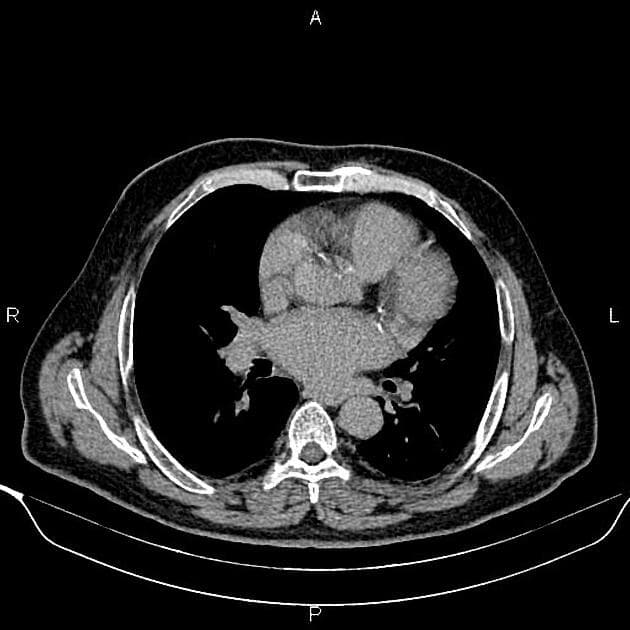

- Một khối nang khu trú một phần lồi ra ngoài (exophytic) kích thước 48 mm, thành dày ngấm thuốc (enhancement) và có các vách ngăn cùng các nốt ngấm thuốc lệch tâm (eccentric enhancing nodules) được ghi nhận ở phần giữa của thận phải.

- Một vài mạch máu tuần hoàn bàng hệ (collateral circulation) nhỏ giãn được ghi nhận trong khoảng gian thận (perinephric space).

Khối nang thận - phân loại Bosniak IV (Renal cystic mass - Bosniak class IV)

- "Các khối nang thận phân loại Bosniak IV có nguy cơ ác tính từ 70-90% và thường là ung thư biểu mô tế bào thận dạng nang."

- "Các đặc điểm hình ảnh chính bao gồm thành dày ngấm thuốc, vách ngăn ngấm thuốc và các nốt ngấm thuốc lệch tâm."